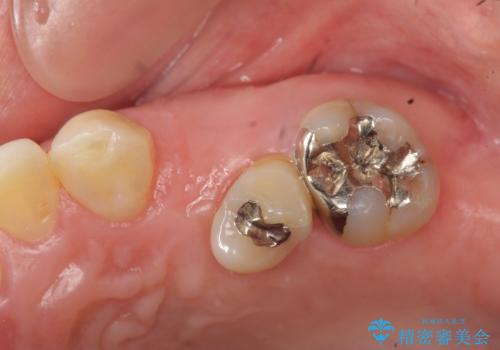

- 左上の歯の喪失し噛みにくいことの改善、歯を入れたいと希望され来院されました。

インプラント治療を行うには隙間が狭すぎるためブリッジか入れ歯をご提案したところ、取り外しの必要な入れ歯は希望されずブリッジを用いて機能・審美性の改善を行っていくこととなりました。

ブリッジの長期的な予後のためには支台となる歯の位置・清掃性が重要となりますが、今回ブリッジを製作するにあたり位置の悪い左上小臼歯を補綴前小矯正を行い位置を改善します。